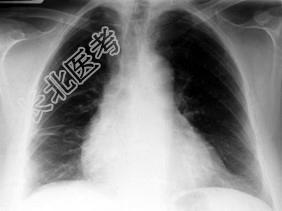

- 单项选择题男,59岁, 呼吸困难,胸痛, 有发热,请结合CT图像选择最可能的诊断 ( )

A、脓胸

B、肺脓肿

C、大叶性肺炎

D、肺囊虫病

E、肺癌